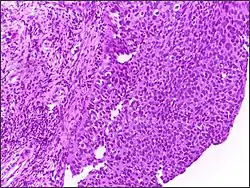

![]() |

Squamous cell carcinoma of cervix | Invasive Squamous Carcinoma of the Cervix. Cold Knife Cone. | Category: Histopathology of squamous cell carcinoma of the cervix | Invasive squamous carcinoma of cervix |